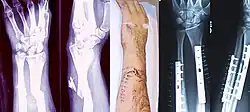

-

Zlomenina radia a ulny a její léčení (dlahy). -